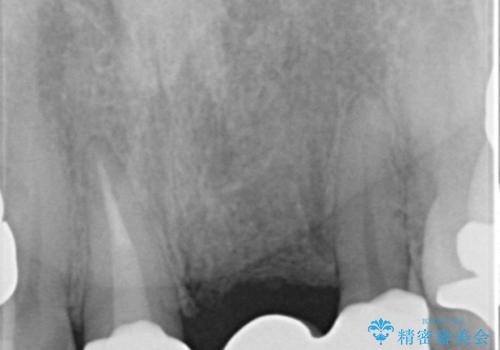

前歯のレジン前装冠(保険内)によるブリッジは、金属で裏打ちされており透明感がなく不自然で、ポンティックも必要以上に長く作られていました。

古いブリッジと金属の土台を除去し、ファイバーコア(金属を使わない強くてしなやかな土台)を植立したのち、オールセラミックのブリッジによる補綴治療を行いました。。